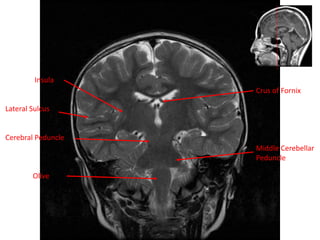

Insula

Lateral Sulcus

Cerebral Peduncle

Olive

Crus of Fornix

Middle Cerebellar

Peduncle

Insula Lateral Sulcus Cerebral Peduncle Olive Crusof Fornix Middle Cerebellar Peduncle